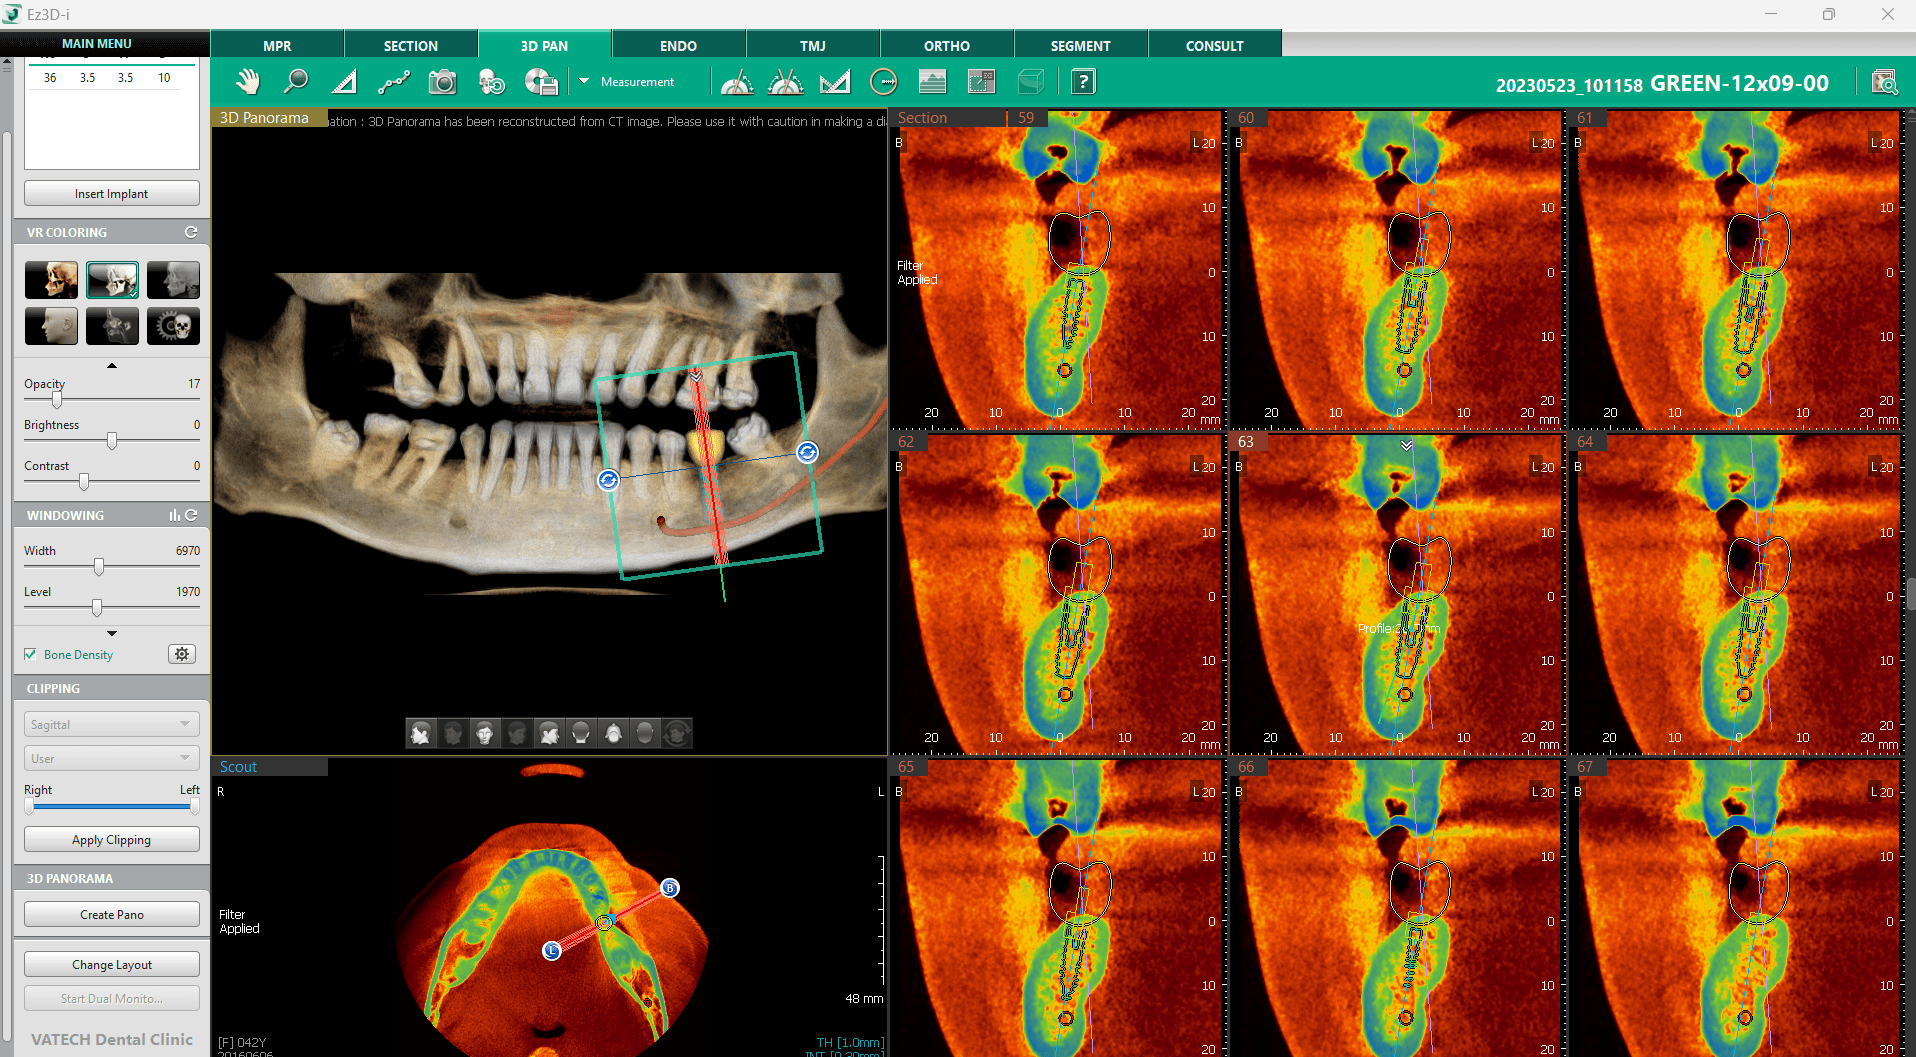

Suprapunerea densității osoase

Pe lângă profilul osos, software-ul include și funcția „Bone Density Overlay”, care suprapune un strat de culori peste imaginile CBCT, indicând diferite niveluri de densitate osoasă conform scalei D1-D5. Împreună cu 3D navigator, aceasta poate fi utilă în timpul procesului de diagnosticare întrucât oferă o imagine de ansamblu rapidă și ușoară a situației din zona viitorului implant.

Activarea acestei funcții se face din secțiunea „Windowing” situată în partea stângă a ecranului, bifând opțiunea „Bone Density”.

Scala de culori se poate ajusta în funcție de necesități, făcând click pe pictograma Setting de lângă caseta de validare. În fereastra de dialog care va apărea, se poate ajusta scala, prin deplasarea liniilor de ghidare verzi, în funcție de nevoi. De asemenea, există posibilitatea de a alege între un gradient de culoare sau o nuanță solidă. Această funcție este extrem de utilă pentru o evaluare rapidă a calității osoase în zona viitorului implant.

Pentru o revenire rapidă la setările originale se poate folosi butonul „Reset the setting”, situat în partea de jos.